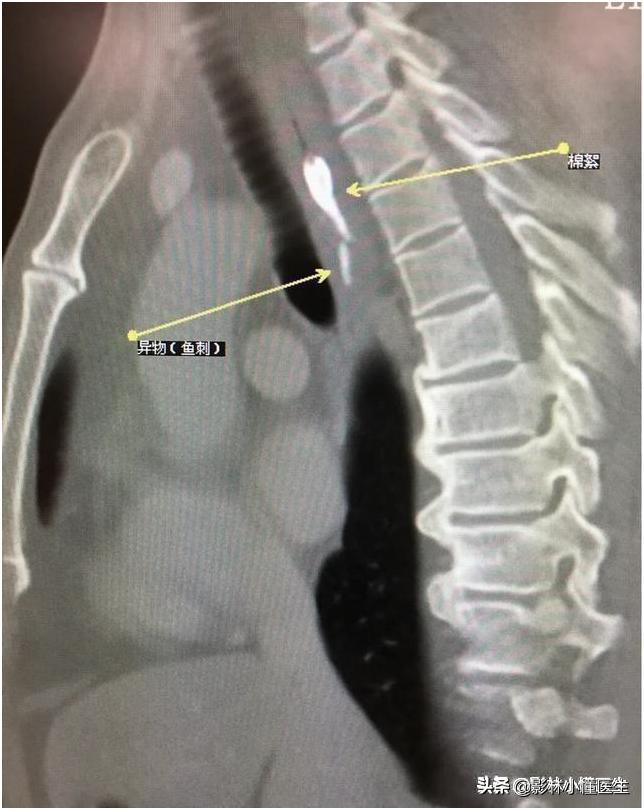

例2

鱼刺刺穿食管及主动脉壁,治疗费用高、预后极差。